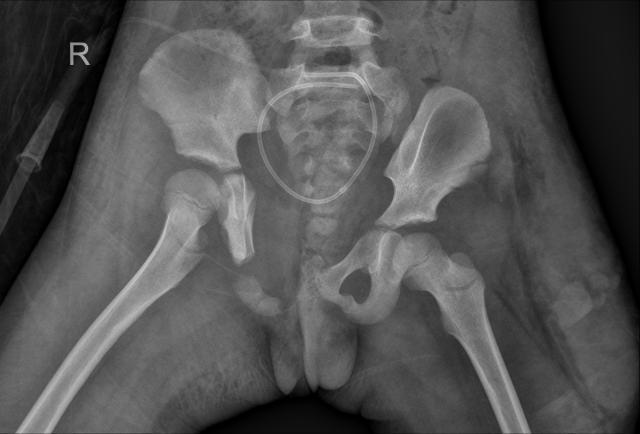

盆环完全断裂,多处粉碎性骨折、脱位、移位,尿道断裂、外阴撕裂……近日一起交通事故中,广西一名4岁女童小花(化名)盆腹部遭到碾压,骨盆几近“散架”,但孩子依然顽强地活了下来。如此重创让见惯了大阵仗的医生们心痛不已,“克服万难也要修复好!”面对复杂严重的伤势,南医三院创伤骨科、妇科、泌尿外科专家在手术台上紧密合作,接力施救,奋战7个小时,终于成功完成了“拼图”式的精准修复。

首先由樊仕才团队主刀,当骨折部位暴露在手术视野中,医生们不禁为这个孩子捏了一把汗:耻骨联合分离,左侧骶髂关节向前方脱位,双侧耻骨、髂骨多处骨折,断端移位,左侧腰骶干神经出现根性撕脱,左髋部及大腿外侧发现大量皮下积血、积液……克服一切困难,也要帮她“拼”回去!

术前